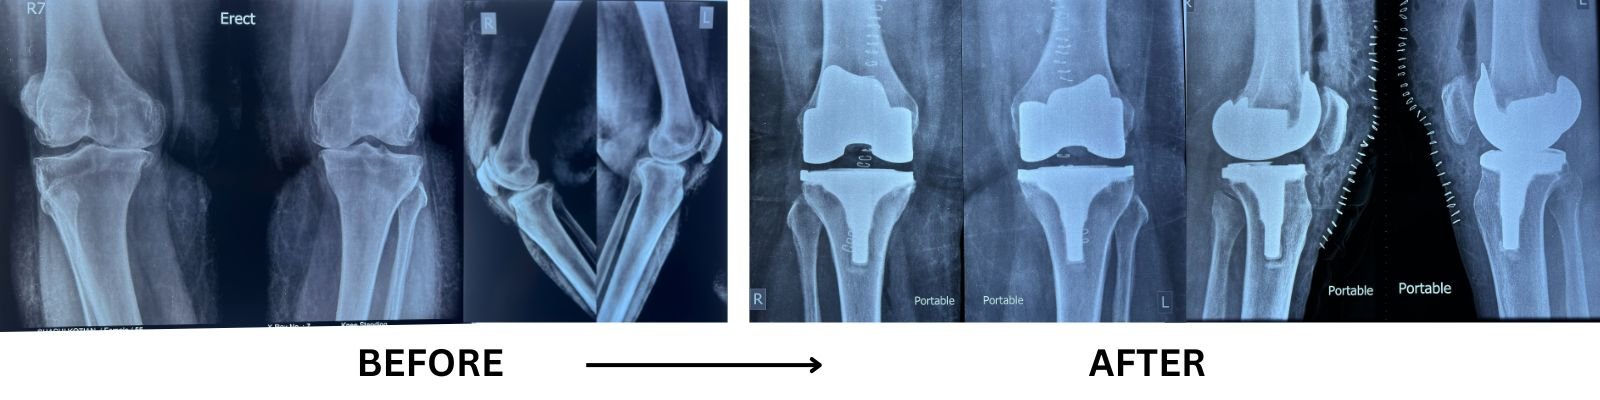

WHAT IS TOTAL KNEE REPLACEMENT

Knee replacement surgery (knee arthroplasty) is a procedure that involves removing diseased or damaged bone and cartilage of a knee joint and replacing them with artificial joint (prosthesis) made of metal, polymers or high-grade plastic parts.

TOTAL KNEE REPLACEMENT DIAGNOSIS